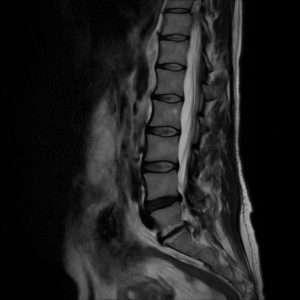

Dlatego wynik rezonansu to tylko część układanki. Najważniejsze są objawy kliniczne i badanie funkcjonalne, które pozwalają dobrać odpowiednią terapię.

Procesy degeneracyjne są naturalnym elementem starzenia.

Choć fizjoterapia nie cofnie zmian strukturalnych, może zatrzymać ich postęp, poprawić stabilność kręgosłupa i zmniejszyć ból.

Regularna praca nad ruchomością i równowagą mięśniową pozwala żyć bez bólu mimo istniejących zmian w dyskach.